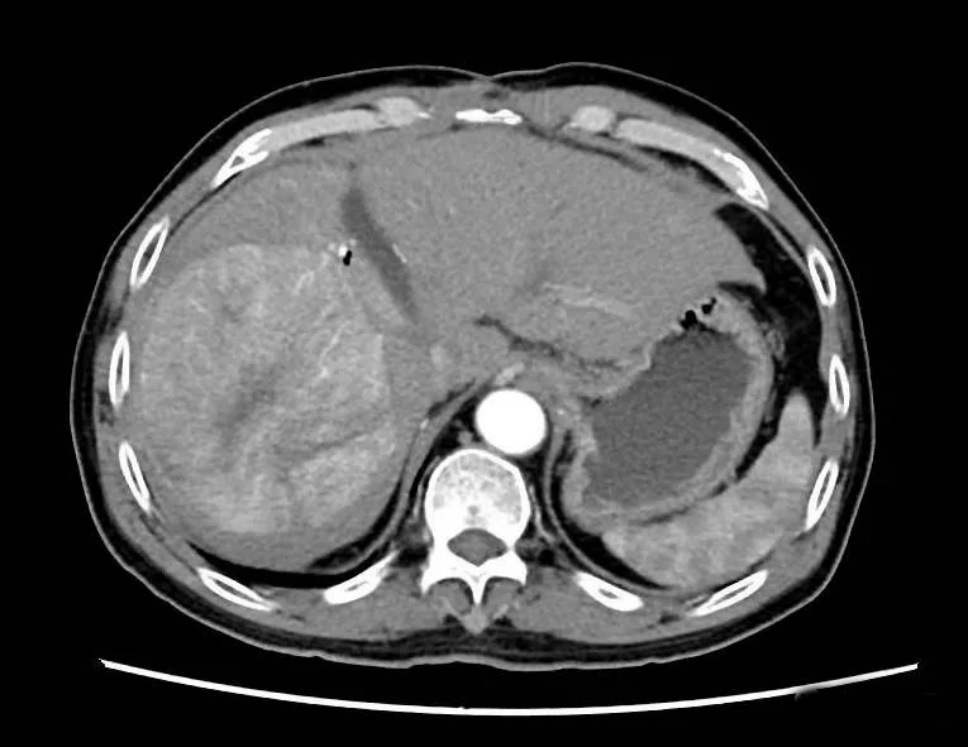

经过精心的术前准备,综合外科肝胆病区团队为患者实施ALPPS第一次手术。术中进行门静脉右支结扎,同时将左右肝分界线肝实质彻底离断。术后两周,CT检查及肝脏三维重建显示,患者右侧肝体积因低血流量而缩小,左肝外叶体积得到一定程度增长,但因患者肝硬化过重,左肝体积增长较慢,未达到二期肝切除标准。再次MDT讨论认为患者体积增加较慢,通过右肝肿瘤TACE(肝动脉化疗栓塞)治疗控制肿瘤进展。